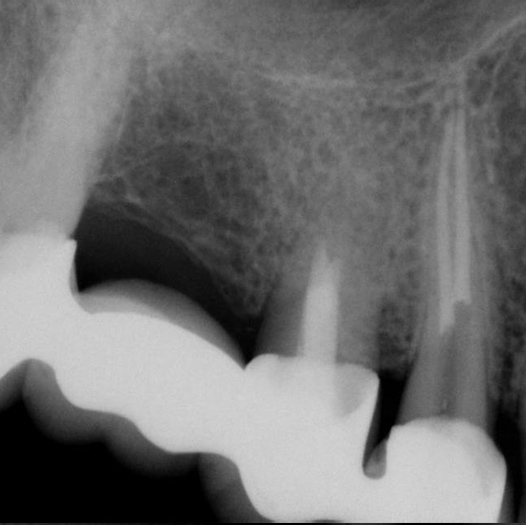

Before

Before Root Canal treatment